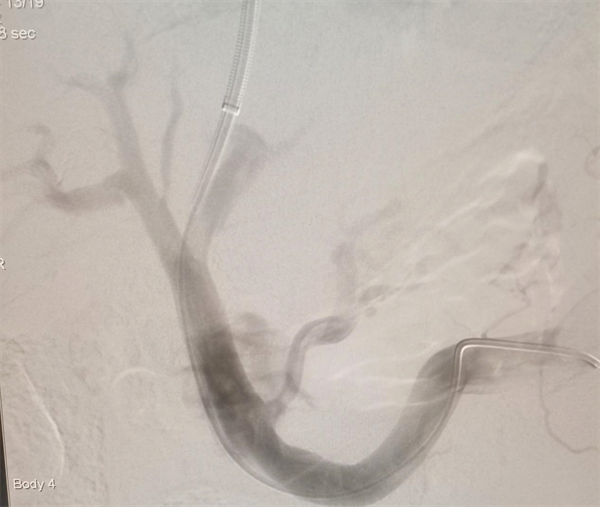

顽固性腹水、食管胃静脉曲张破裂出血是肝硬化门静脉高压最常见的并发症,大多病情危重或生活质量极差,对于有大量腹水、黄疸、肝功能严重受损的病人,进行外科手术,临床疗效差,死亡率很高。经颈内静脉肝内门体分流术(TIPS),基本原理是用Seldinger技术穿刺颈静脉,建立颈静脉-上腔静脉-右心房-下腔静脉-肝静脉通路,从肝静脉或下腔静脉肝段穿刺门静脉分支或矢状部并建立门-体分流的人工通道,能迅速有效、且持续性地降低门静脉压力,实现止血、缓解顽固性腹水、预防消化道出血等目的,具有疗效确切、创伤小、术后恢复快的特点。

TIPS手术涵盖了穿刺、造影、测压、球囊扩张、支架置入、血管栓塞等多项技术操作,其中在透视下由肝静脉向门静脉穿刺尤为困难,被认为是代表了外周介入的最高水平,此次手术成功说明犍为县人民医院的介入诊疗水平又上一个新台阶。(供稿:犍为县人民医院 王春蓉 余鹏)